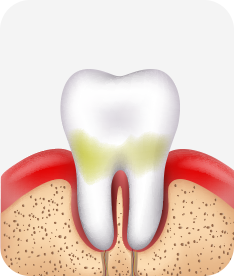

치주염 단계별 증상

건강한 상태

치아 주위의 잇몸이 핑크색을 띄며, 잇몸에서 피가 나지 않음.

스케일링을 6개월 ~ 1년 주기로 받고 올바른 칫솔질로 건강한 치주 조직을 유지

치은염 (초기~중기)

치아 주위의 잇몸이 붉게 부어 있으며, 칫솔질 등을 할 때 피가 남.

스케일링 주기의 조절이 필요할 수 있으며, 올바른 칫솔질을 시행하여야 함.